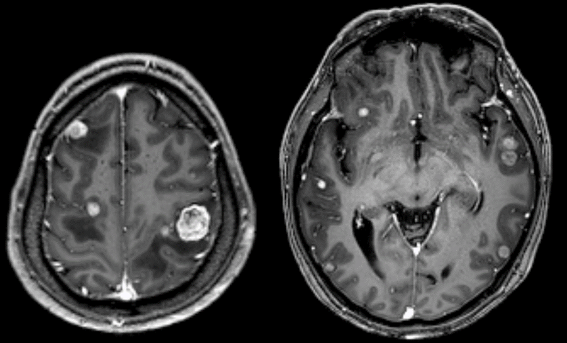

1. 脑转移瘤

原发肿瘤病史,可发生于任何年龄,以 40-60 岁多见。

转移部位:幕上多见,70%-80% 为多发,多位于皮髓质交界区。

CT:平扫肿瘤呈高、低、等或混杂密度,小者为实性结节,大者中间多有坏死,呈不规则环状。病灶周围有瘤周水肿,增强后瘤灶强化。

MRI:长 T1、长 T2 信号,瘤周水肿广泛,占位效应明显,增强后实性肿瘤明显强化,坏死囊变可呈环形、不规则结节状强化。